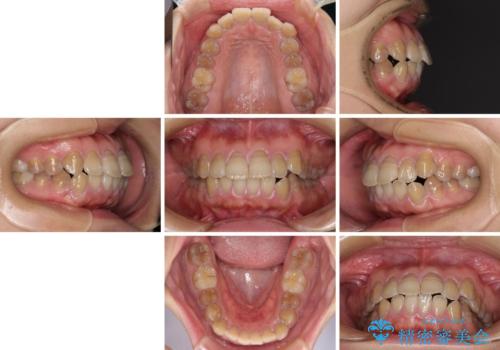

横顔の印象が大きく変わる ワイヤー装置での抜歯矯正

- 口元の突出感を気にして来院された患者様です。

上下前歯が著しく前突している状態であったので、上下左右の第1小臼歯4本を抜歯し、ワイヤー装置にて矯正治療を行うこととしました。

舌の突出癖により、前突になったと考えられたため、舌のトレーニングをしっかりと行うよう指導しました。

4本の歯を抜歯したことで、飛び出していた口元が引っ込み、横顔が大きく改善されました。